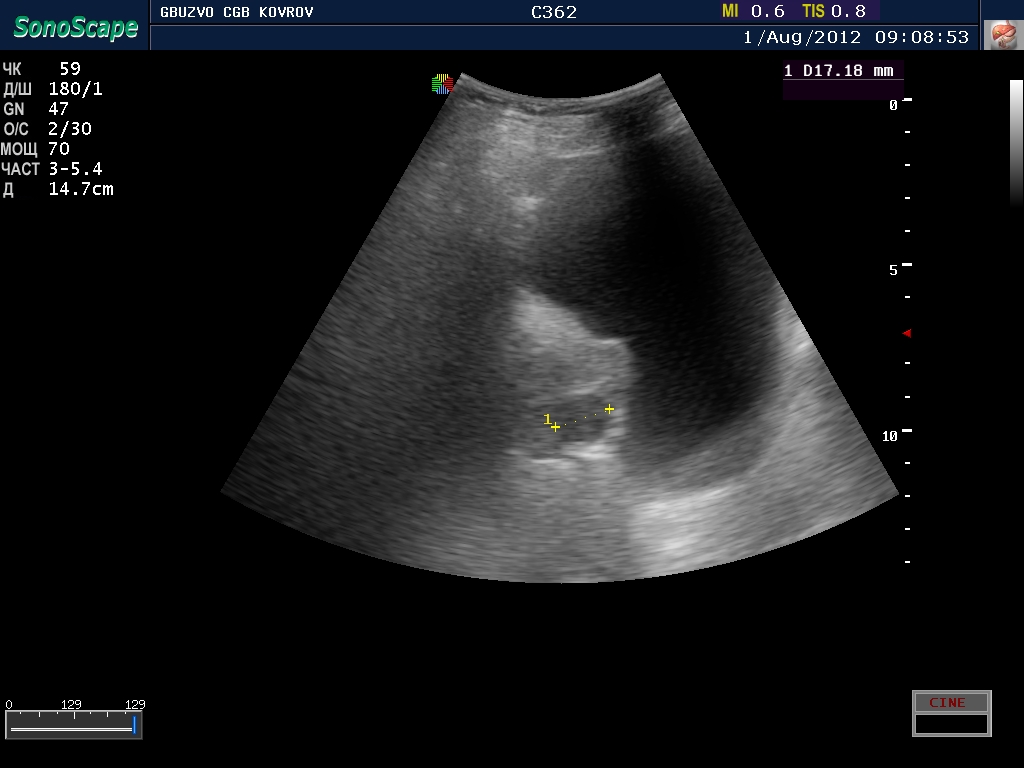

В простате лоцируется гипоэхогенное округлое образование - вопрос - как трактовать?

простатическая часть уретры или очаг?

V-мочевого пузыря 450 мл , стенка 7 мм в ней псведодивертикулы Vост - 380мл, V простаты 36 мл

Вроде как клиническая проблема есть. Сначала была у меня тенденция трактовать это как очаг, но потом рука дрогнула и я решил не заметить сей факт..норма?